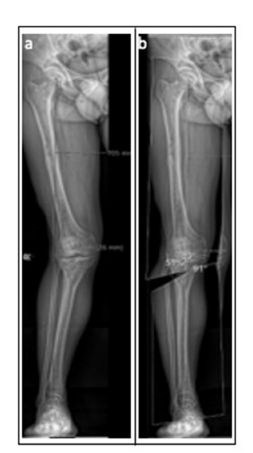

A 33-year-old male presented with lateral knee pain and gait disturbance. He had sustained femoral and tibial plateau fractures on the right side 25 years ago due to a motor vehicle accident, which were treated by osteosynthesis. Clinical evaluation revealed a valgus deformity and limb shortening. Examination showed a limping gait, genu valgum and recurvatum with full range of motion. Ligamentous stability was preserved except for a positive Lachman test. MRI confirmed grade II chondromalacia in the lateral compartment. The patient worked in a physically demanding job as a warehouseman and had no comorbidities (Figure 1).

Figure 1:A) Preoperative analysis revealed a valgus axis of 21°, a mechanical medial proximal tibial angle (mMPTA)

of 108° and a mechanical lateral distal femoral angle (mLDFA) of 89°.

B) A varus correction of 16° via lateral open wedge HTO was planned, resulting in a postoperative mMPTA of 91°

and a JLCA of 1°.